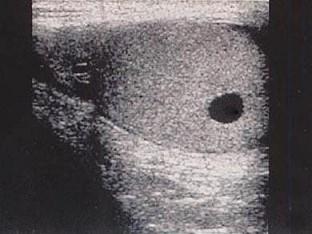

问题 患者体检发现睾丸小肿块,结合超声图像,最可能的诊断是?(?)

选项 A.睾丸囊肿 B.睾丸结核 C.白膜囊肿 D.睾丸腺癌 E.附睾囊肿

答案 A